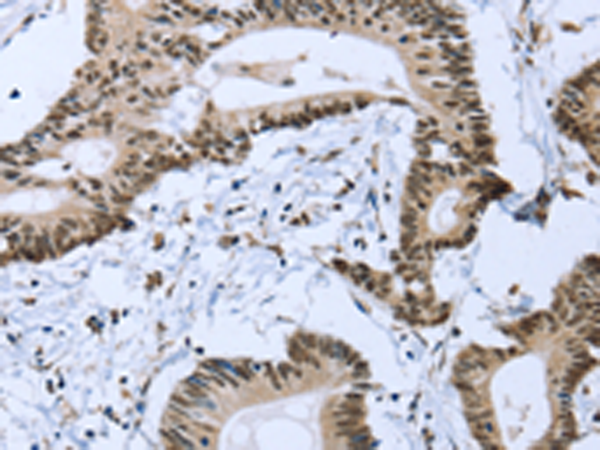

分类: 科研抗体货号: P08594别名: CT16; CT16.1; CT16.2; GAGEE1; PAGE-5应用: IHC反应种属: Human